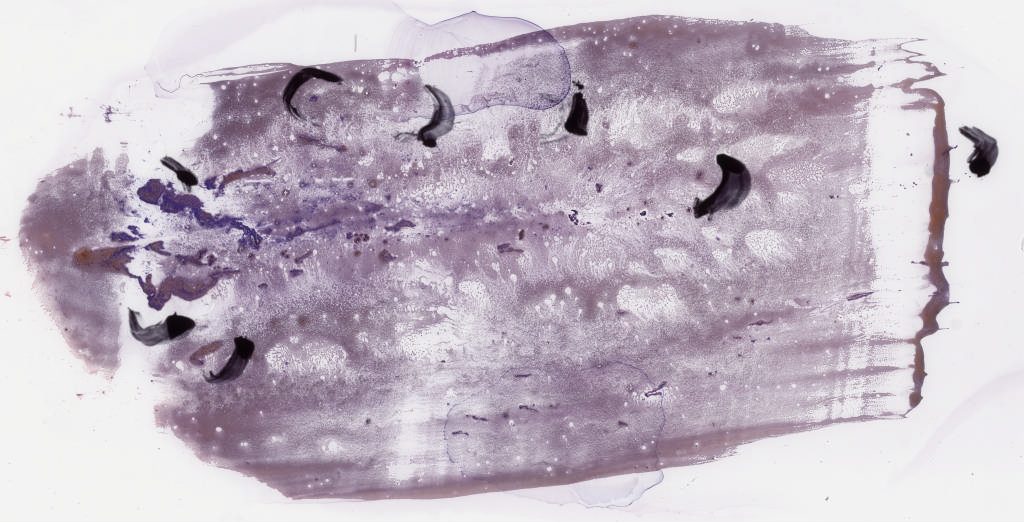

1791970.svs

151391

x

77309

@

40X